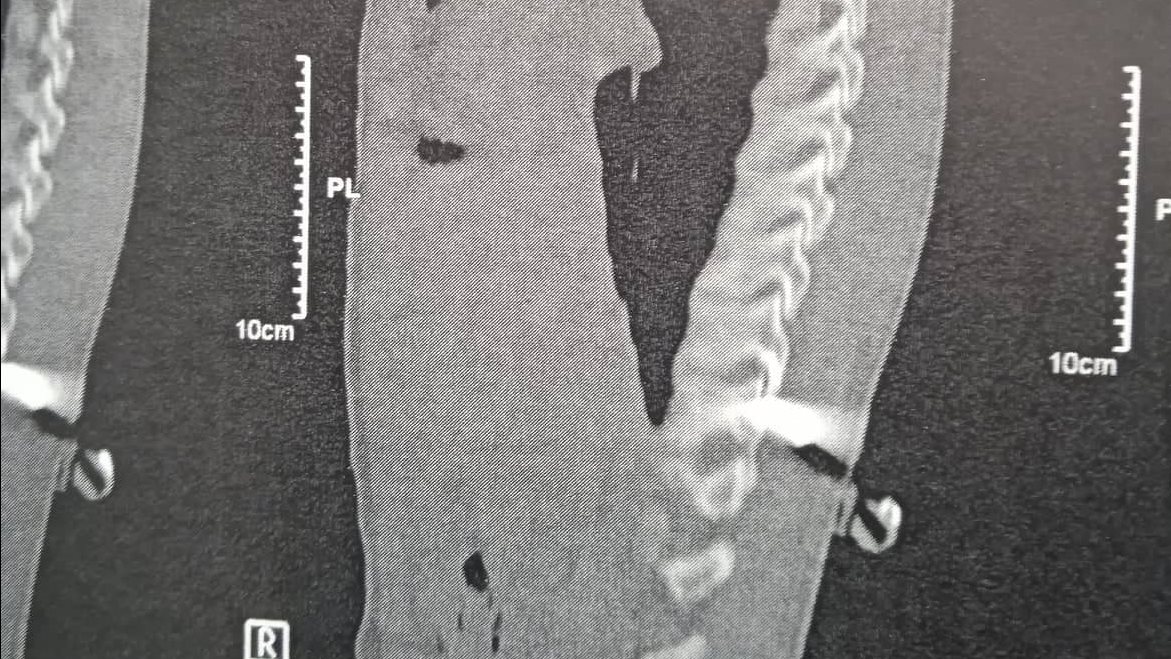

تمكن فريق من أطباء مستشفى الأحرار التعليمى بمدينة الزقازيق، بقيادة الدكتور عيد فتح الله النجار، استشاري جراحة المخ والأعصاب وجراحة العمود الفقري، وبمساعدة الدكتور درويش أخصائي جراحة المخ والأعصاب، وبإشراف أطباء تخدير الطوارئ وتمريض مستشفى الأحرار، من إنقاذ طالب بمدينة الإبراهيمية أصيب خلال مشاجرة نشبت بينه وبين زميله بطعنة بمنتصف العمود الفقري حيث تم إجراء جراحة دقيقة أنقذته من شلل محقق.

أكد الدكتور عيد النجار أن الطالب والذي يبلغ من العمر 15 عاما وبعد إصابته بطعنة نافذة بالظهر كاد أن يعاني من شلل بالطرف السفلي الأيمن، وذلك نتيجة تعرضه لجرح نافذ بسلاح أبيض مطواة قرن غزال ولكن تمكن الفريق الطبي من إجراء جراحة دقيقة و ناجحة أنقذته من شلل محقق، و لكن سيتأثر الطرف الأيمن ببعض الضعف الذي يمكن علاجه بسهولة وسيتماثل الطالب للشفاء التام وسيكون باستطاعته المشى مرة أخرى.